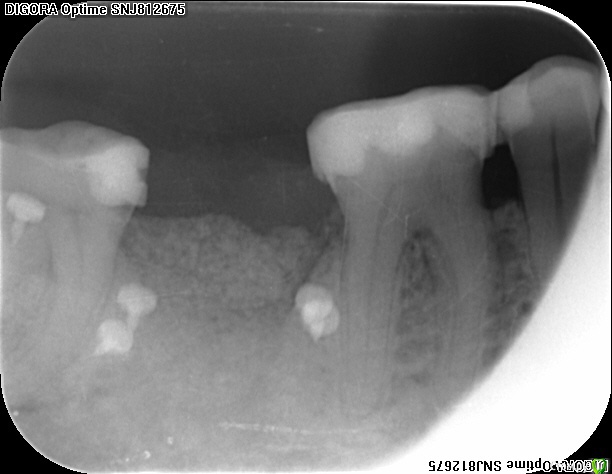

an_ver Опубликовано 4 ноября, 2015 Поделиться Опубликовано 4 ноября, 2015 Только что))...хрусть-хрусть))) Апатос,Эволюшн толстая,пины Углич,ручки Тринон,шовный Унифлекс 5/0. 1 Ссылка на комментарий

IvanK Опубликовано 4 ноября, 2015 Поделиться Опубликовано 4 ноября, 2015 Только что))...хрусть-хрусть))) Апатос,Эволюшн толстая,пины Углич,ручки Тринон,шовный Унифлекс 5/0.А зачем снимок? Ссылка на комментарий

an_ver Опубликовано 4 ноября, 2015 Поделиться Опубликовано 4 ноября, 2015 А зачем снимок?Порадоваться))) 1 Ссылка на комментарий